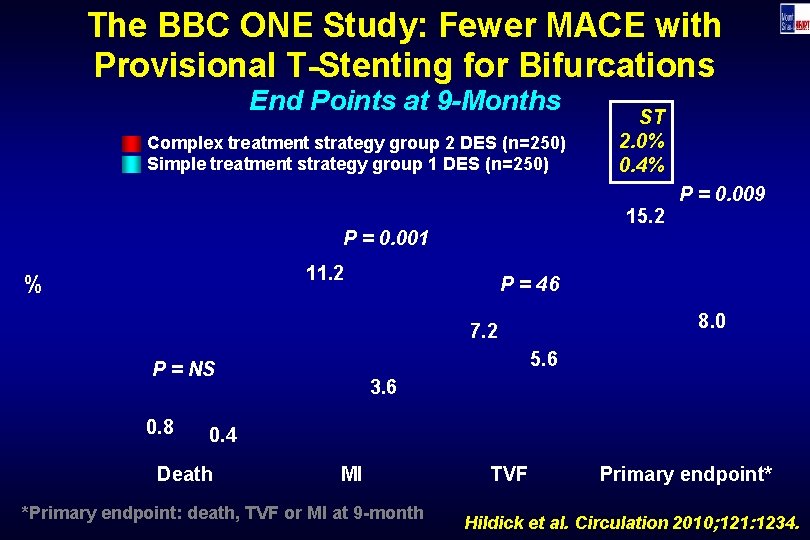

The BBC ONE Study: Fewer MACE with Provisional T-Stenting for Bifurcations End Points at 9 -Months Complex treatment strategy group 2 DES (n=250) Simple treatment strategy group 1 DES (n=250) 15. 2 P = 0. 001 11. 2 % P = 0. 009 P = 46 8. 0 7. 2 5. 6 P = NS 0. 8 ST 2. 0% 0. 4% 3. 6 0. 4 Death MI *Primary endpoint: death, TVF or MI at 9 -month TVF Primary endpoint* Hildick et al. Circulation 2010; 121: 1234.